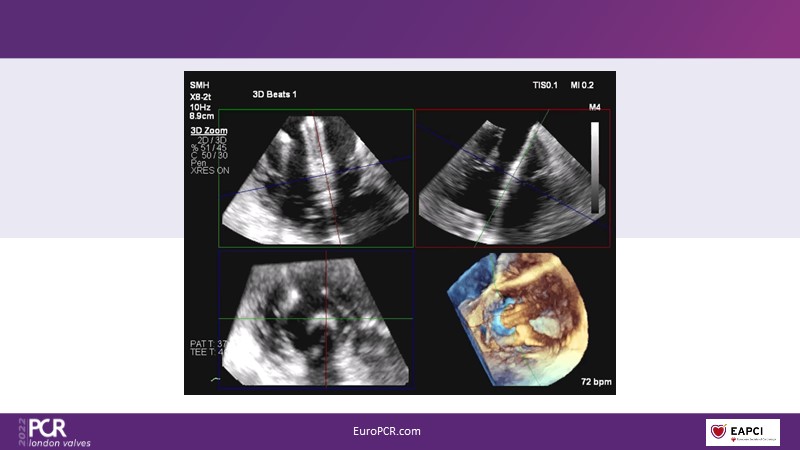

The right valves for the right ventricle: Venus MedTech tricuspid and pulmonary replacement systems

In this session from PCR London Valves 2022, discover the new Venus MedTech technology for tricuspid and pulmonary valve replacement, and a review of the clinical indications, selection criteria and procedural details.

- To learn about Venus MedTech technology, clinical indications and procedural details of valve replacement systems

- To learn more about the clinical experience and outcomes with Cardiovalve tricuspid and Venus P-valve